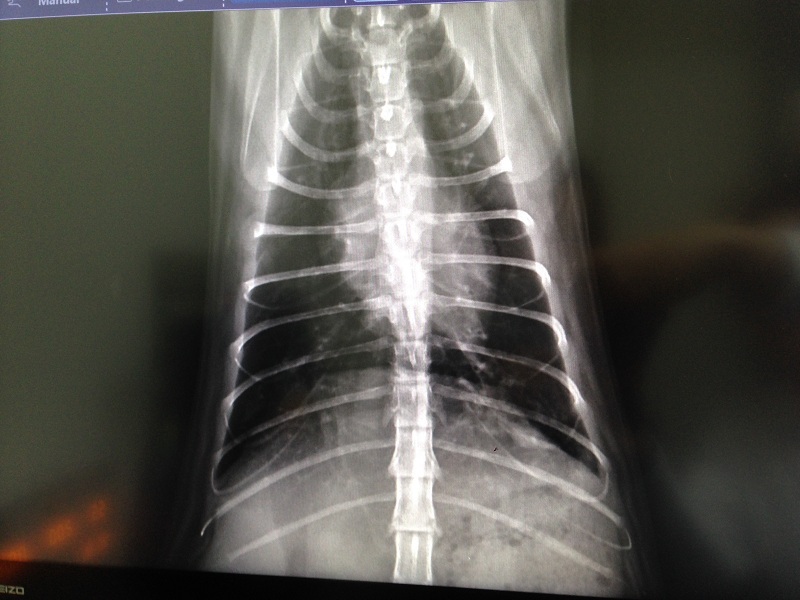

3/21 澄諾回診 喵喵 體重4.62KG

【就診狀況】

回診前幾日喵喵可售的次數變多

所以今日回診時拍攝了不同角度的肺部X光

由X光中看出左肺的白色結點叫右肺多且要來的霧

可算是肺炎的前期,此次的藥物加開類固醇來減緩咳嗽的症狀

但怕肺部中有細菌無法借咳嗽排出體外,故會同時加開抗生素